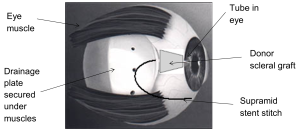

During the operation, one end of the tube is securely inserted into the front part of the eye. The other end is connected to a white silicon plate that rests on the surface of the eye (sclera), underneath the eye lid. This plate acts like a reservoir for the fluid from inside the eye to be drained away.

A membrane called the conjunctiva covers the front of the eye and lines the inside of the eyelids. It covers the silicon plate and absorbs the fluid that collects in it. As the fluid can now drain through the newly created drainage channel, your eye pressure will be reduced.

When the tube-shunt is first put in, the eye surgeon will partially close it with a stitch called a Supramid stent stitch. This helps to prevent too much fluid coming out of the eye which would cause the eye pressure to be too low.

The glaucoma tube-shunt is going to stay in the eye for the rest of the person’s life, so we need to cover the portion of the tube outside the eye. This prevents the tube from moving and becoming exposed. To do this, we can either use a donor scleral patch graft (see figure 2) or a Tutoplast scleral patch graft.

It is a piece of sclera (the white tissue of the eye) and it is attached to the eye using stitches.